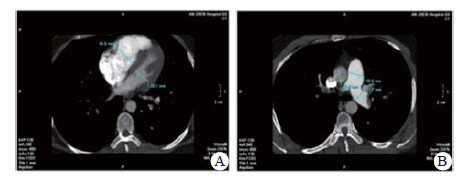

实验室检查结果:动脉血气分析pH 7.458, PaO2 60.5 mmHg, PaCO2 26.7 mmHg, SpO2 92.0%;D-二聚体2 655 ng/mL; BNP 163.00 pg/mL; 血常规WBC 5.91 ×1012/L, NE 73.8%, HGB 138.0 g/L, PLT 286 g/L; 同型半胱氨酸(HCY)14.0 μmol/L (正常值:6~14 μmol/L); 纤维蛋白原定量(FBG) 0.520 g/L(正常值:2.000~4.000 g/L), 纤溶酶原活性39.0%(73.0%~127.0%), 纤溶酶原抑制物-1(PAI-1)6.898 ng/mL(正常均数4.207 ng/mL), 组织纤溶酶原激活物(t-PA) 5.135 μg/L(正常均数2.375 μg/L); 血浆抗凝血酶Ⅲ(AT-Ⅲ:A)、血浆蛋白C活性(PC:a)、血浆蛋白S活性(PS:a)以及狼疮抗凝剂(Lupus anticoagulant, LA)水平在正常范围内。行经胸壁超声心动图检查提示右心扩大(因肺动脉瓣及三尖瓣反流极少, 无法准确估测肺动脉压力), 肺动脉增强CT(pulmonary artery computed tomography angiography, CTPA)提示右室扩大、两肺动脉主干及分支可见多发充盈缺损(图 2)。下肢静脉多普勒超声提示右侧腘静脉急性深静脉血栓形成及右侧股浅静脉血栓形成, 左侧髂静脉及左下肢深静脉未见明显异常。诊断为急性PE(高危组)、KTS。评估后给予重组组织型纤溶酶原激活物(r-tPA)50 mg 2 h内静脉泵入溶栓治疗, 溶栓过程中(r-tPA使用至35 mg时)患者出现咯血约200 mL, 遂被迫停止溶栓治疗, 监测活化凝血时间(accelerated clotting time, ACT)降至200s时给予普通肝素持续泵入并维持ACT于180~220 s, 肝素抗凝治疗48 h后改为低分子肝素(low molecular weight heparin, LMWH)联合华法林治疗, 期间未再发生咯血症状。入院第4天完善肺通气/灌注显像检查, 并提示:左肺下叶, 右肺中叶内段(亚段)、中叶外段、下叶前基底段、外基底段、后基底段血流灌注可见放射性分布稀疏缺损区, 双肺多发PE(累及8个肺段及1个亚肺段), 肺血流灌注受损范围占双肺容积的51%;入院10 d后复查CTPA, 结果显示两肺动脉主干腔内充盈缺损完全消失(图 3)。住院治疗15 d患者好转出院, 院外口服华法林抗凝治疗, 定期监测国际标准化比值(INR), 且维持于PE治疗范围2~3之间。抗凝治疗1年后进行肺通气/灌注显像复查, 提示右肺下叶前基底段、外基底段血流灌注改善, 左肺下叶, 右肺中叶内侧(亚段)、中叶外段、下叶后基底段血流灌注恢复正常。随访3年以来, 患者院外规律服用华法林抗凝治疗, 定期监测INR, 定期复查超声心动图及肺通气/灌注显像检查, 出院3个月超声心动图检查肺动脉压力正常、三尖瓣反流消失; 出院12个月及33个月复查肺通气/灌注未见新发的血流灌注稀疏缺损区, 出院33个月复查双髂双下肢静脉超声未见明显阻塞, 随访期间未出现出血或其他不良事件, 出院1个月后恢复工作至今, 一般状况良好。

| 图 3 患者溶栓后10 d复查CTPA, 右室扩张明显好转(A)、肺动脉增宽有所缓解(B) |